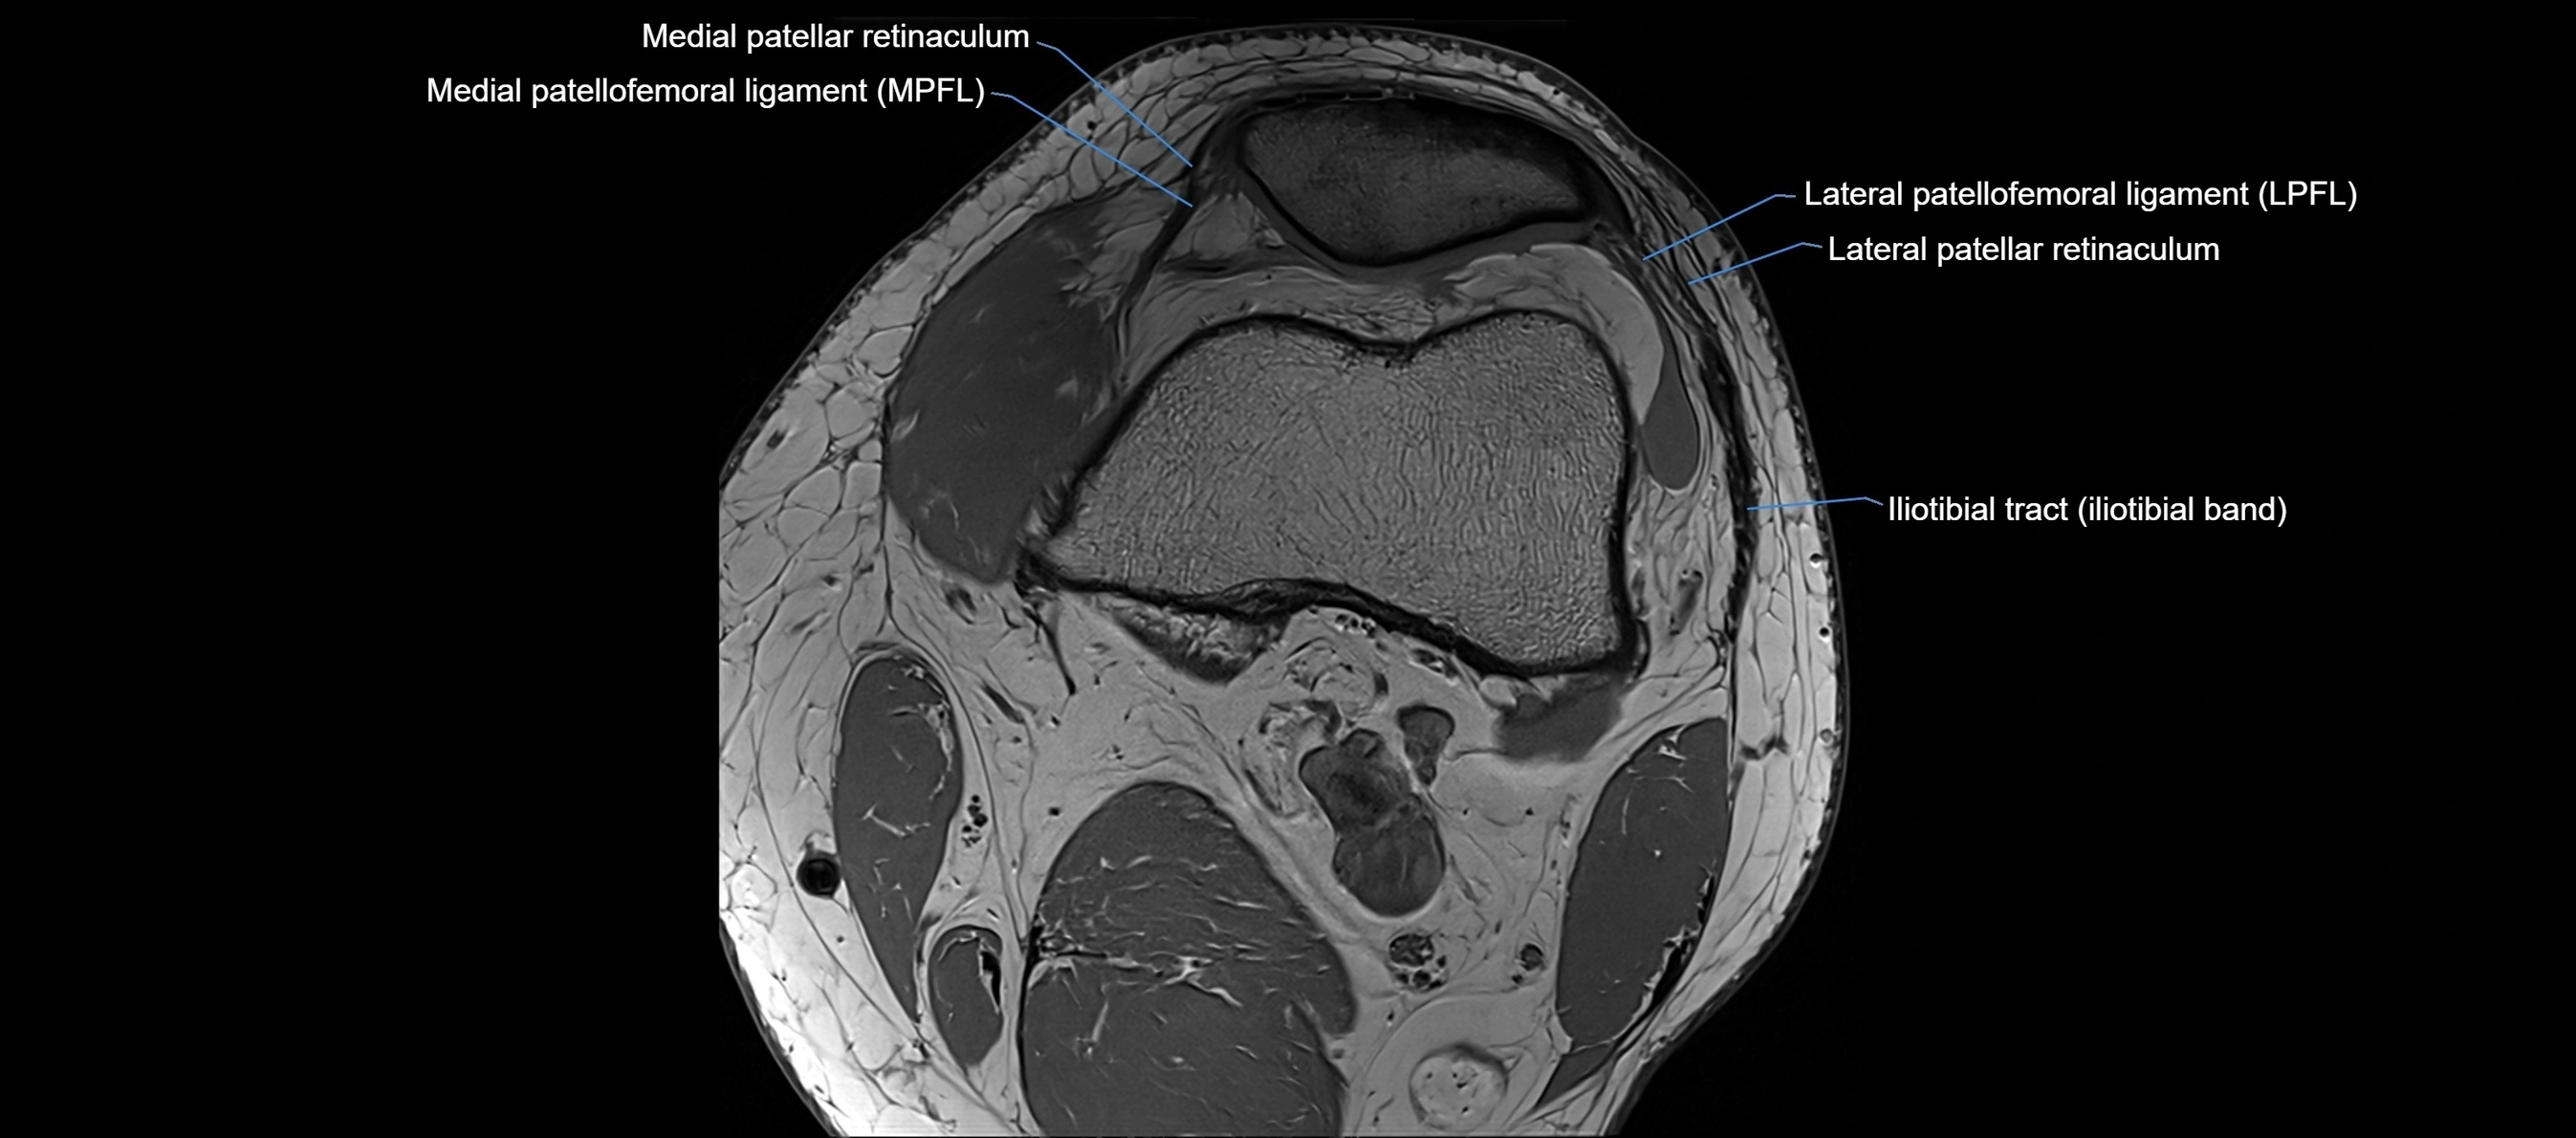

MRI images

image